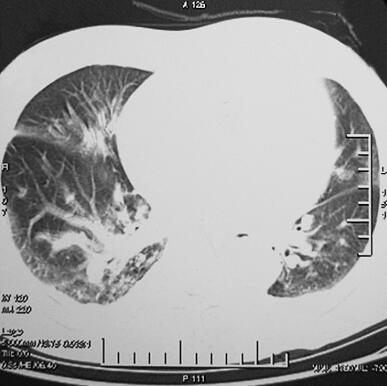

4月2日胸部CT(图1)示双肺见小片状高密度影,以右肺为著,双侧胸腔积液,少量心包积液。痰培养未找到致病菌,4月4日调整抗生素,给予美罗培南1.0g,每12小时1次,静脉滴注抗感染治疗。同时多次查血生化,血Na+均显著降低,多波动于105~115mmol/L,并伴有神志淡漠,予以限水及补钠未见效。为明确顽固性低钠血症的原因,与内分泌科讨论后行血ACTH、皮质醇节律及24小时尿钠定量。结果显示患者血ACTH及血皮质醇均明显低于正常,24小时尿钠在正常范围内,考虑存在腺垂体功能减退症,行垂体MRI及甲状腺功能检查。垂体MRI示空泡蝶鞍,甲状腺功能正常。遂给予氢化可的松100mg静脉滴注,每日2次,4月18日复查血生化K+ 4.53mmol/L,Na+ 130mmol/L,Cl− 98mmol/L,当天停用美罗培南,改为莫西沙星0.4g静脉滴注,每日1次,连续应用3天。4月25日复查胸部CT(图2)示感染征象已控制,准予出院。

图1 2011年4月2日胸部CT